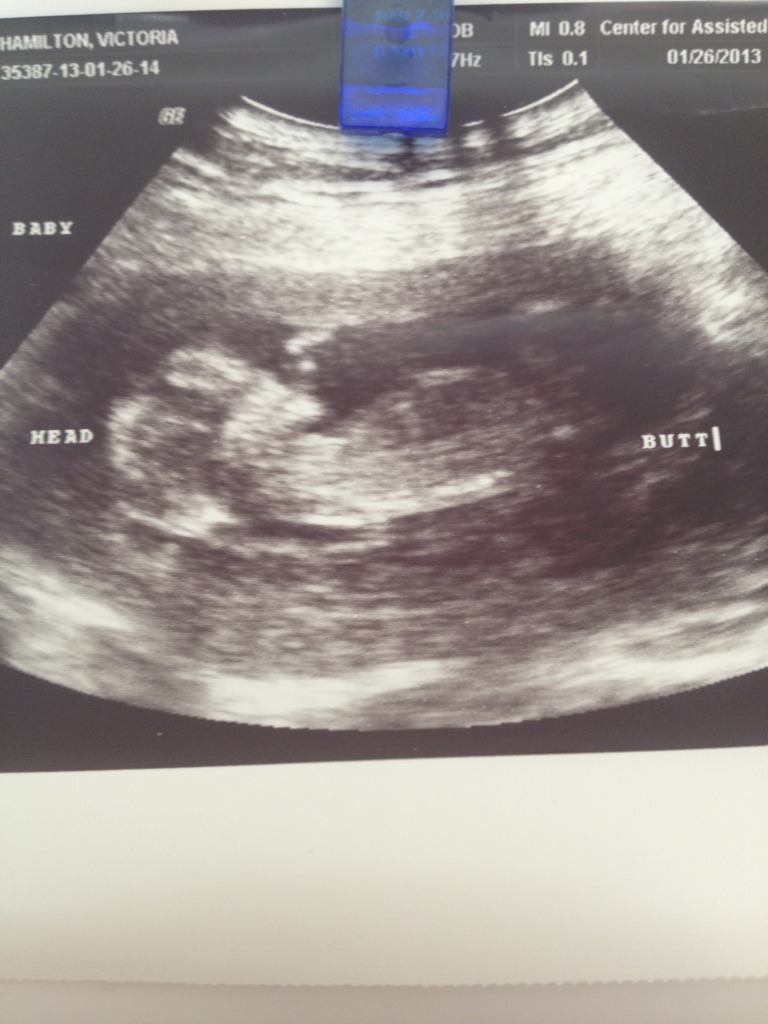

I don't think there's any clues but maybe someone may have an idea. The tech wouldn't show us anything and the whole NT scan was like 5 minutes. Attachment 8396

Hard to see if there is a nub? If that white dot is a nub then leaning girl.

i'm leaning girl, but it's hard to tell...

Leaning girl

Leaning girl also:)

Maybe girl if its the nub.. x

thinking girl